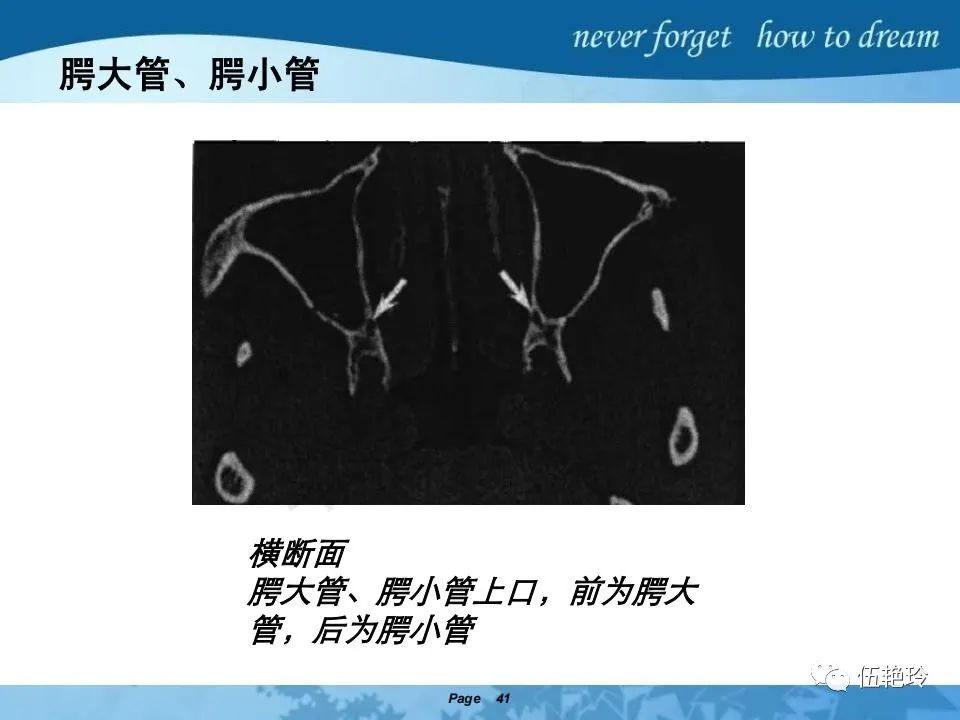

翼腭窝的解剖结构与鼻咽癌侵犯

2.31 向上颅内:①鼻咽顶壁→破裂孔(岩尖、斜坡)→蝶窦、海绵窦;②鼻咽顶壁→蝶骨基底部→蝶窦、海绵窦;③鼻咽侧壁→茎突前间隙→蝶骨大翼(卵圆孔)→海绵窦;④鼻咽侧壁→茎突前间隙→翼腭窝→ 颞下窝;⑤鼻咽前壁→鼻腔→翼突、翼腭窝→眶下裂→眶尖→海绵窦;⑥鼻咽前壁→鼻腔→上颌窦、筛窦;